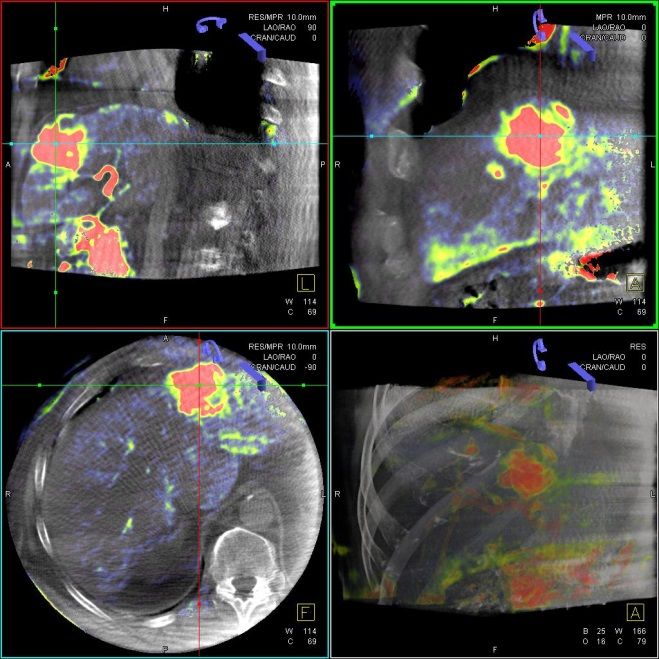

Selektive Interne Radio-Therapie (SIRT)

Die Selektive Interne Radiotherapie (SIRT) wird in der Fachliteratur auch Radioembolisation (RE) genannt. Hierbei werden gezielt kleine, radioaktive Kügelchen, sog. Mikrosphären, über den Katheter (siehe TACE) von mehreren Positionen in der Leber mit dem Blutstrom in das gut durchblutete Tumorgewebe gebracht und bleiben dort in den kleinen Gefäßen "stecken", die den Tumor ernähren. Von dort bestrahlt das in den Kügelchen enthaltene radioaktive Element Yttrium-90 über mehrere Tage hinweg das Tumorgewebe und zerstört es selektiv. Dieses Verfahren kann bei Leberkrebs oder -metastasen eingesetzt werden, wenn die Herde trotz Chemotherapie weiter wachsen und nicht chirurgisch oder mittels RFA und TACE behandelbar sind.

Das Verfahren wird von der interventionellen Radiologie zusammen mit der Partnerabteilung der Nuklearmedizin sowie den entsprechenden Partnerkliniken geplant und durchgeführt.